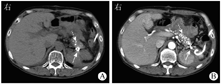

于2019年8月7日急诊行腹腔动脉造影+脾动脉瘤栓塞术(图3),术中经右侧股动脉穿刺置管后,引入5 F Corba导管行腹腔干造影,见脾动脉一条分支中段造影剂外漏,形成假性动脉瘤。经微导管超选择脾动脉出血分支,于破口远端和近端分别予6 mm×2 mm弹簧圈各2枚栓塞,复查造影栓塞满意。最后经Corba导管行腹腔干造影未见明显造影剂外渗,弹簧圈均在位。术后静脉滴注奥美拉唑40 mg(1次/d)抑酸护胃,加贝酯300 mg(1次/d)静脉滴注抑制胰酶活性。患者全身营养状况显著改善后,于2020年10月13日行全身麻醉下胰管切开取石+胰管-空肠吻合+广泛肠粘连松解术,术中见胰腺组织明显萎缩,质地硬,胰尾和脾周致密粘连,胰体尾部假性囊肿与周围组织紧密粘连难以剥离,且易出血。于胰腺表面纵行切开至胰管,沿主胰管纵行切开约5 cm,取出其内结石。取距离十二指肠悬韧带远端约25 cm处空肠,经结肠后方,以可吸收缝线行胰管-空肠侧侧吻合。取距离胰肠吻合口远端约50 cm处空肠,与胰肠吻合口近端空肠行空肠-空肠侧侧吻合。丝线扎闭胰肠吻合口近端肠段,完成非离断式(uncut) Roux-en-Y吻合。2020年10月16日上腹部CT平扫加增强扫描检查(图4)可见胰腺头颈部和部分体部多发点状高密度影,胰腺尾部可见金属伪影,增强扫描无明显强化,周围见部分渗出。术后予以醋酸奥曲肽注射液抑制胰腺分泌,并行窦道造影后以0.9%氯化钠溶液反复冲洗引流管,2周后患者引流液明显减少,无发热、畏寒等不适,予以出院。患者出院后定期复查,胰腺假性囊肿持续置管引流,每日引流约20 mL淡黄色透明液体。2021年3月28日起患者胰腺假性囊肿引流液呈乳糜样(图5),每日引流量为20~30 mL,无畏寒、发热。

2019年8月7日入院体格检查示体温为36.5 ℃,脉率为78次/min,呼吸频率为20次/min,血压为120/80 mmHg(1 mmHg=0.133 kPa),精神尚可,可自行步入病房,神志清楚,无贫血貌,皮肤、巩膜轻度黄染,浅表淋巴结无肿大,心肺未见明显异常;腹平软,未见胃肠型和蠕动波,未见腹壁静脉曲张,中上腹轻压痛,无反跳痛,未扪及包块,肝脾肋下未扪及,墨菲征阴性,腹部叩诊鼓音,肝肾区无叩击痛,移动性浊音阴性,肠鸣音为4次/min,双下肢无水肿。血常规检查示白细胞计数为3.7×109/L,中性粒细胞占比为0.495,血红蛋白为101 g/L,血细胞比容为31.20%,血小板计数为336×109/L、超敏C反应蛋白为3.89 mg/L;血清淀粉酶为214 U/L。尿常规、粪常规+粪便隐血试验、肝肾功能、血清电解质、凝血功能、肿瘤标志物、甲状腺功能、自身抗体系列、免疫球蛋白G4、人类免疫缺陷病毒、梅毒螺旋体抗体均阴性。2019年8月7日上腹部CT增强扫描检查(图1、图2)提示慢性胰腺炎急性发作、胰腺多发结石,胰体尾部巨大假性囊肿,假性囊肿内脾动脉假性动脉瘤可能,脾囊肿。2019年8月8日磁共振胰胆管造影(magnetic resonance cholangiopancreatography,MRCP)示左右肝管、肝总管、胆总管粗细不均,局部显示不清,但未见扩张,其内未见明显充盈缺损,胰腺体尾部和脾门区见一长径约10 cm的类长圆形异常信号影,T1、T2加权像均呈混杂信号。脾脏外侧及其后方见一囊状水样信号,长径约7 cm。2020年10月13日入院体格检查示腹部有一长约10 cm手术切口,左侧脾窝穿刺引流管在位,引流液较少,腹软,腹部无压痛和反跳痛。血常规检查示白细胞计数为6.8×109/L,血清淀粉酶为196 U/L。假性囊肿引流液李凡他试验弱阳性,乳糜试验阳性,淀粉酶>12 000 U/L。上腹部CT增强扫描检查示慢性胰腺炎腹部术后,术区及其周围改变。